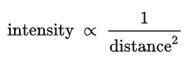

Figure 1. Penetration of NIR energy into a human cadaver using the Vielight Neuro.

Das Vielight Neuro ist für eine maximale Übertragung der Lichtenergie ausgelegt.

- Die Lichtenergie wird bei der Ausbreitung über Entfernungen schwächer, weil die inverse square law of light.

Angesichts dieser beiden Faktoren sind Helme/Hüte usw. nicht ideal für die Photobiomodulation des Gehirns. Zusätzlich zu dem Energieverlust, der entsteht, wenn das Licht aus dem Helm/der Mütze/dem Hut usw. austritt, werden die Haare zu einer Hemmschwelle, da sie das Restlicht absorbieren, da die schwebenden LEDs keinen Kontakt mit der Haut haben.